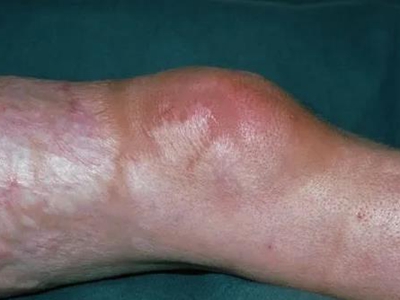

局限性硬皮病症状图片

局限性硬皮病是硬皮病的一种类型,属于慢性结缔组织病。典型皮损表现为局部皮肤变硬、萎缩,一般无内脏受累,依据皮损特点主要表现为斑块状、线状。病因不明,可能与外伤、皮肤感染、遗传等原因有关。

局限性硬皮病主要累及皮肤,一般无内脏受累,主要表现为皮肤变硬、萎缩。斑块状硬皮病在躯干多见,初为一个或数个淡红或紫红色水肿性斑片,椭圆或不规则形,钱币大小或更大,数周或数个月后皮损扩大,中央逐渐凹陷,呈象牙或黄白色,周围绕以淡红或淡紫色晕,触之似皮革,久之皮损表面光滑、干燥、无汗、毳毛消失,数年后停止扩展,硬度减轻,局部萎缩变薄,留有色素沉着或减退。

有时皮损如线状,常沿单侧肢体或肋间神经分布,进展迅速,常引起肢体挛缩及骨发育障碍。皮损发生在面额中央时,局部可呈线状显著凹陷,菲薄的皮肤紧贴于骨面,形成刀砍状,有时合并颜面偏侧萎缩,累及头皮时可出现脱发。